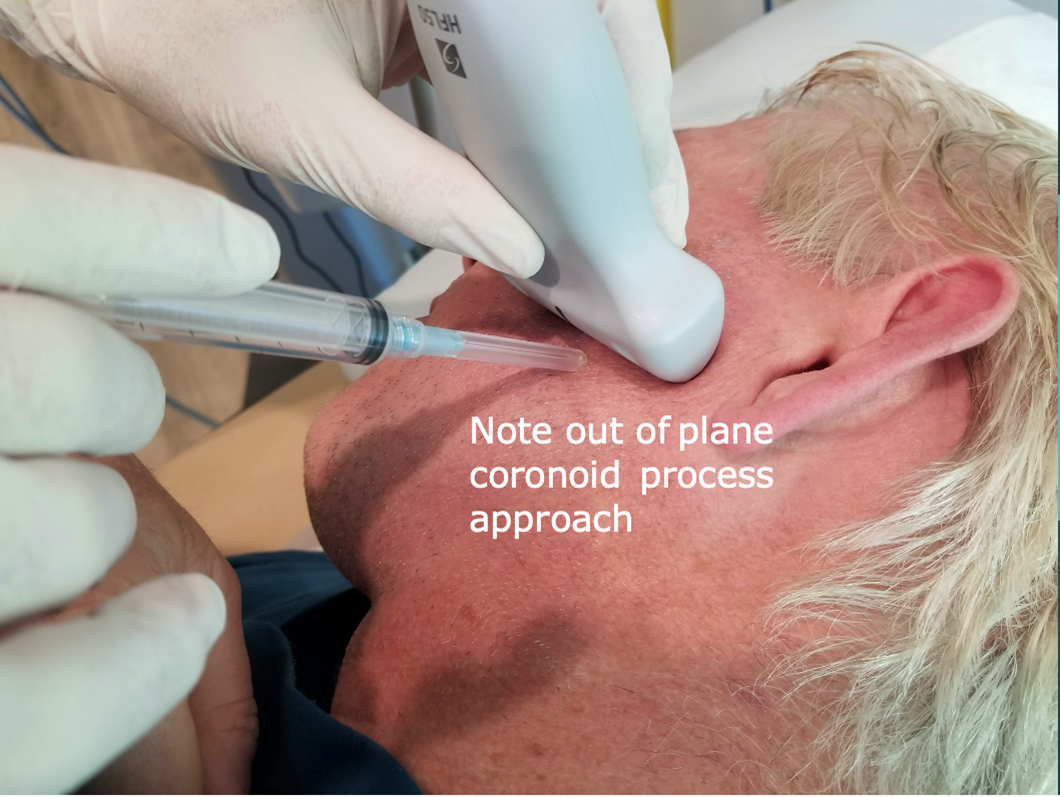

Following this, the probe is rotated 90 degrees to a transverse orientation. The mandibular coronoid process enthesis is then injected out of plane with 0.5 ml injectant. (Figures 6 and 7).

Figure 6: Injection approach: Coronoid process